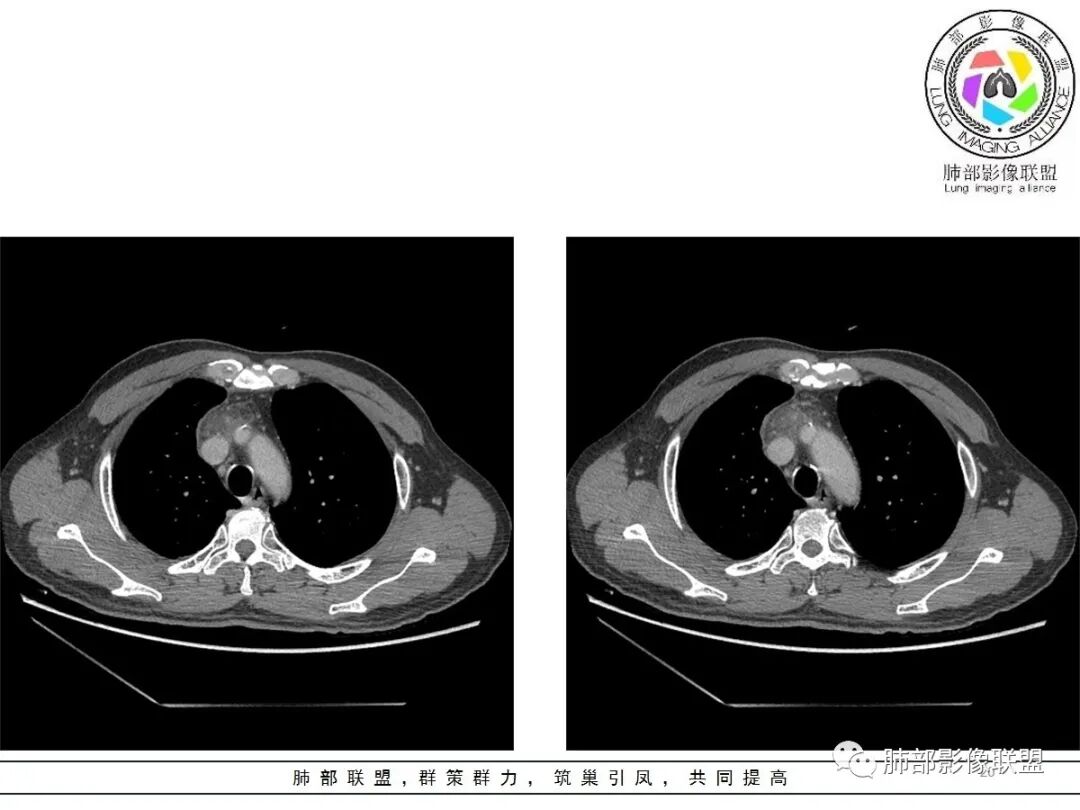

19日,4天后, 内部低密度影有,周围渗出增多,胸水增多

薄膜状强化

影像上周围病灶变化明显

常规肿瘤侵犯不支持,太快

应该是炎性病变渗出

脂肪密度明显,还有钙化、囊性病变,支持含脂质类病变破裂

周围是化学性炎症或出血所致

后期强化,可能与炎症有关

可能:1、肿瘤或瘤样病变破裂出血或内部物质外溢所致2、炎性病变所致

肿瘤样病变破裂所致纵隔炎应该没错

南边:肿瘤或肿瘤样病变破裂所致纵隔炎,这是大方向

结果:符合B型胸腺瘤伴出血,坏死囊性变,局部脓肿形成

4.四天内病灶变化快,块影增大且不规则,包膜似不完整,边界不清,上份可见浸润或渗出,与周围心脏大血管及心包等间隙不清。胸水增多。

第一次的检查符合胸腺瘤影像学改变,短期内的形态学改变及突然出现的边界模糊或浸润等,符合出血或炎症。